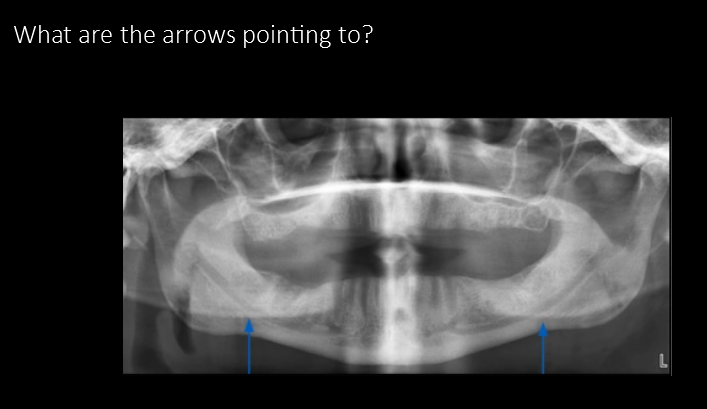

What are the arrows pointing to?

Ghost image of mandible